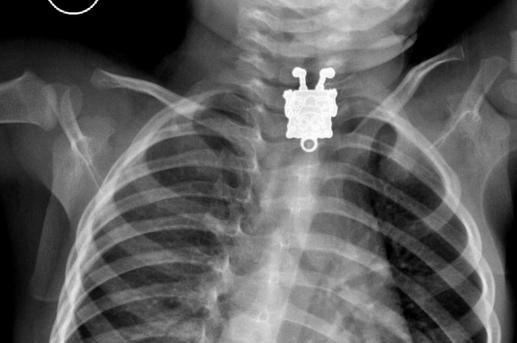

إحدى هذه الحالات استقبلها الأطباء في مستشفي الملك عبدالعزيز بجدة، حيث أحضر أحد الآباء طفله الذي يبلغ من العمر 16 شهراً بعد أن ابتلع قطعة غير معروفة، وبعد إجراء الأشعة فوجئ الأطباء بوجود لعبة "سبونج بوب"، الشخصية الكرتونية الشهيرة داخل مريء الطفل!

وكانت القطعة التي ابتلعها الطفل للشخصية الكرتونية مرتدية الحذاء وتبتسم وتخرج لسانها، ومن المرجح أن الطفل أزال هذه القطعة من قلادة لشقيقه وابتلعها أثناء اللعب بها، وقد أجرى الأطباء عملية عاجلة للطفل وتمكنوا من استخراج هذه القطعة بنجاح.